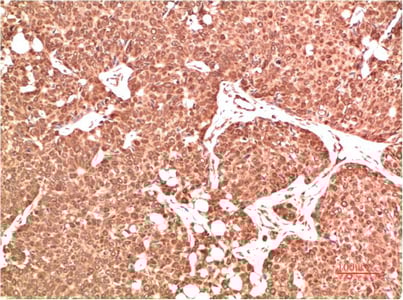

IHC (Immunohistochemistry)

The ATM atm (Catalog #AAA293814) is an Antibody produced from Rabbit and is intended for research purposes only. The product is available for immediate purchase. The ATM Rabbit Polyclonal Antibody reacts with Human, Mouse, Rat and may cross-react with other species as described in the data sheet. AAA Biotech's ATM can be used in a range of immunoassay formats including, but not limited to, IHC (Immunohistochemistry). Researchers should empirically determine the suitability of the ATM atm for an application not listed in the data sheet. Researchers commonly develop new applications and it is an integral, important part of the investigative research process. It is sometimes possible for the material contained within the vial of "ATM, Polyclonal Antibody" to become dispersed throughout the inside of the vial, particularly around the seal of said vial, during shipment and storage. We always suggest centrifuging these vials to consolidate all of the liquid away from the lid and to the bottom of the vial prior to opening. Please be advised that certain products may require dry ice for shipping and that, if this is the case, an additional dry ice fee may also be required.Precautions